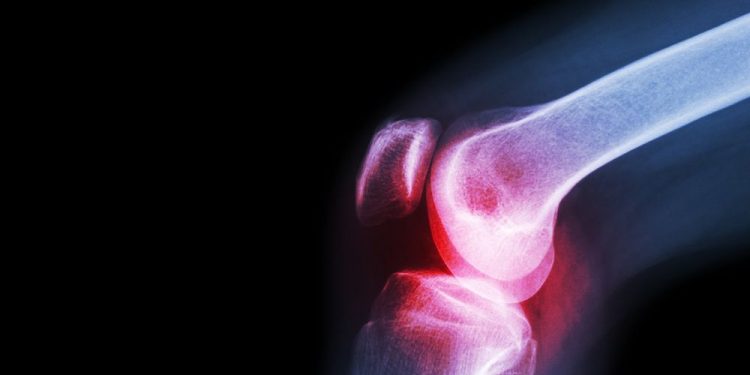

They will also take a sample of the infected joint fluid to check for white blood cells and bacteria. If you have an X-ray or MRI scan, your doctor will also take pictures of the joint and examine it to see what is causing the symptoms.

These tests can be very important in diagnosing septic arthritis, because they can help doctors see what is happening to the joint. They can also tell your doctor how well the antibiotics are working and if your child’s symptoms are improving.